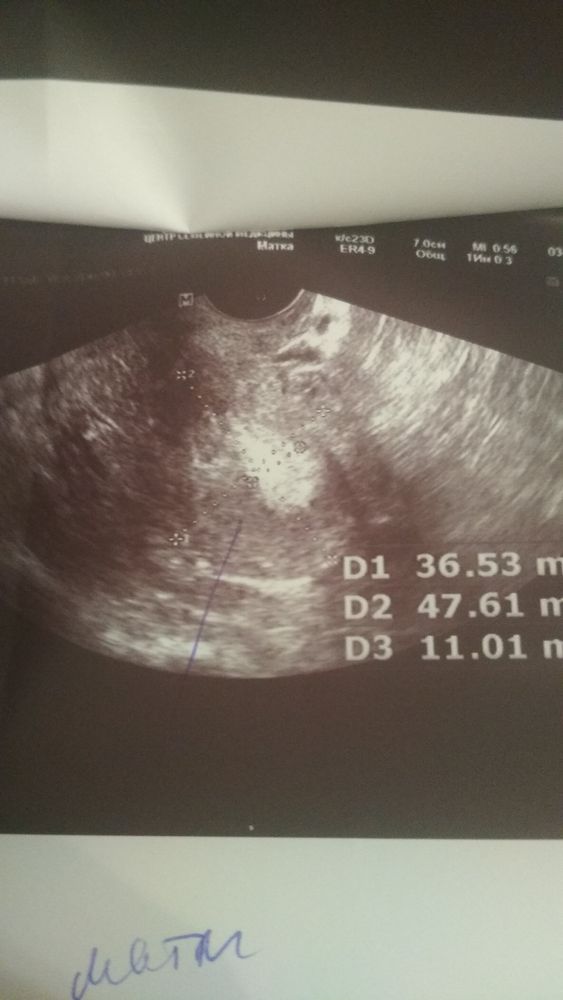

Здравствуйте, Дамы. История такова. Если кратко, мне 33, беременность первая (дай Бог, чтобы это была она). Случилась задержка, тесты были еле положительные с первого дня задержки по шестой ( сегодня уже 11), я пришла в жк, меня про всё спросили, признаки особо не искала, чтобы себя не обнадеживать. Меня беспокоила ТТ каждый вечер до 37.5 (падала сама, ничего не пила, БТ 37.7 с момента задержки и небольшие тянущие ощущения со стороны левого, а потом правого яичника. При осмотре Г сказала что матка мягкая, взяла мазок, отправила на УЗИ И ХГЧ. Я, не подумав, что лучше сначала сделать Хгч, отправилась на УЗИ в мед. Центр. Делали Трансвагинальное, пять минут не совсем аккуратно мне там искали ПЯ. Ничего не нашли не в трубах, ни в матке. Единственное что мне сказала узист, что эндометрий 11 это хорошо. Но а мне то что. Хгч я смогу сдать только через четыре дня. Нервов больше нет, особых признаков нет, грудь не болит, не внушаю себе ничего, потому что устала надеяться. Если среди вас найдутся те, кто поймёт снимок и объяснит описание протокола, я буду вам очень благодарна.